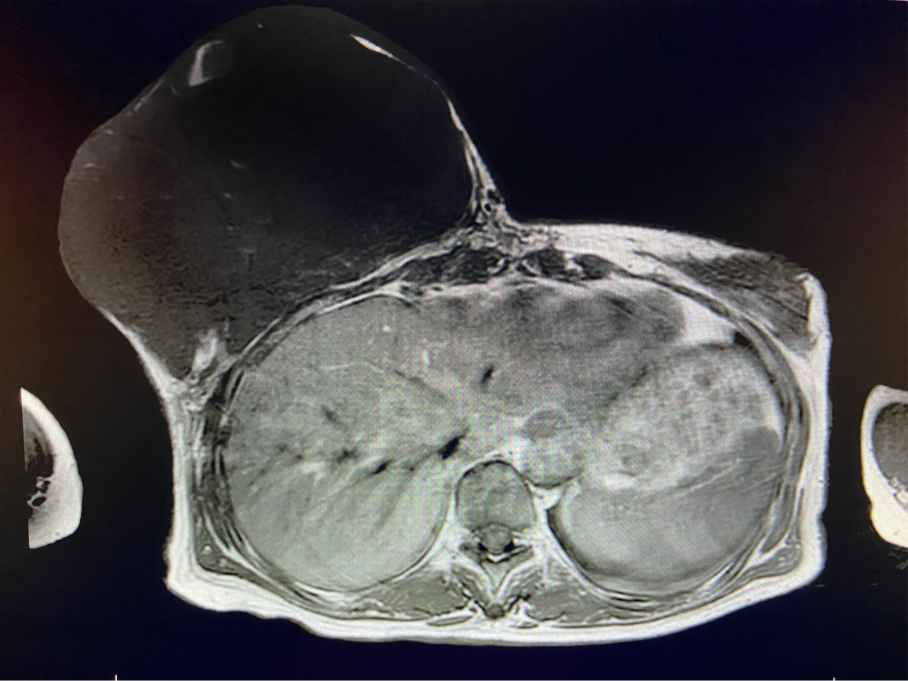

6個(gè)月前,王女士能感覺(jué)到右乳腫物明顯增大至“鴨蛋”一般,而且伴有局部皮膚瘙癢及輕度脹痛,可這次王女士并沒(méi)有那么幸運(yùn),服藥3個(gè)月不僅沒(méi)有控制住腫物,脹痛也越發(fā)嚴(yán)重,超聲檢查提示:右乳囊實(shí)性占位,最大前后徑約10.8cm,右腋窩多發(fā)腫大淋巴結(jié),遂行右乳腫物穿刺活檢術(shù),術(shù)后病理檢查提示:右乳腫物穿刺乳腺組織2條,均可見(jiàn)導(dǎo)管囊性擴(kuò)張,部分區(qū)域間質(zhì)纖維增生,其中1條內(nèi)導(dǎo)管上皮成普通型增生。輾轉(zhuǎn)當(dāng)?shù)囟嗉裔t(yī)院藥物治療后,錢沒(méi)有少花,但是療效甚微。

2周前,王女士的右乳外下方皮膚破潰,伴大量滲液,還發(fā)出陣陣惡臭。經(jīng)多方打聽(tīng),王女士從外地來(lái)到西安國(guó)際醫(yī)學(xué)中心醫(yī)院甲乳外科劉曉敏主任處就診。入院后,迅速完善了一系列相關(guān)術(shù)前檢查:王女士的雙乳外形不對(duì)稱,右乳約22?20cm,皮膚水腫明顯并可見(jiàn)靜脈曲張。右乳外下象限皮膚可見(jiàn)局部破潰,創(chuàng)面有3處,共約6?4cm大小,創(chuàng)面呈暗紅色,伴有血性滲出及惡臭,局部皮膚溫度升高。右側(cè)腋窩可觸及腫大淋巴結(jié)。

該患者右乳巨大腫物術(shù)前初步考慮乳腺葉狀腫瘤可能,因腫瘤太大,幾乎遍及整個(gè)右側(cè)乳房,為保證“無(wú)瘤原則”,術(shù)中切除范圍位置未知,極有可能出現(xiàn)皮瓣缺損。于是,經(jīng)過(guò)和整形醫(yī)院郭樹(shù)忠院長(zhǎng)、整形外科王愛(ài)武主任的討論,提供了兩種手術(shù)方式,一是創(chuàng)面修復(fù)(植皮或轉(zhuǎn)移皮瓣修復(fù)創(chuàng)面),二是乳房再造,與患者及家屬溝通后,決定先解決腫物,3年病情不再?gòu)?fù)發(fā)后,可以再考慮乳房重建。